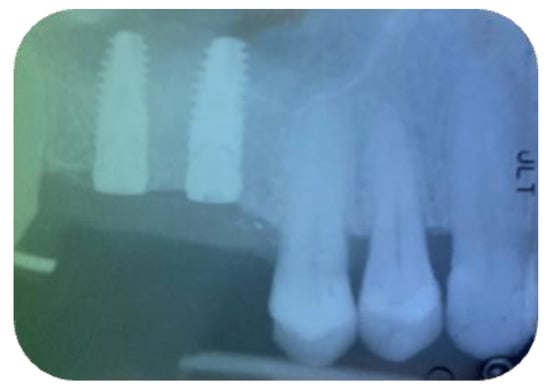

2.1. Surgical Procedures